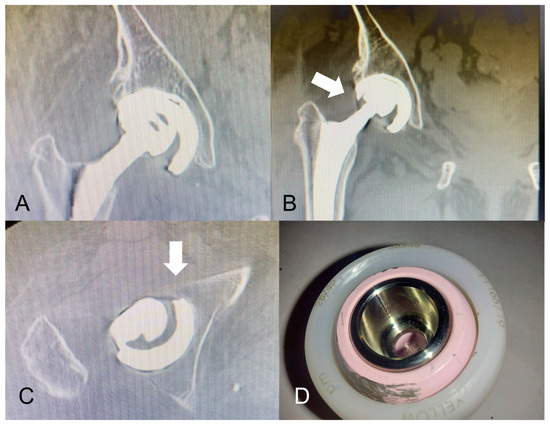

- Chalmers, B.P.; Dubin, J.; Westrich, G.H. Modular dual-mobility liner malseating: A radiographic analysis. Arthroplast. Today 2020, 6, 699–703. [Google Scholar] [CrossRef]

- Romero, J.; Wach, A.; Silberberg, S.; Chiu, Y.F.; Westrich, G.; Wright, T.M.; Padgett, D.E. 2020 Otto Aufranc Award: Malseating of modular dual mobility liners. Bone Joint J. 2020, 102 (Suppl. S7), 20–26. [Google Scholar] [CrossRef]